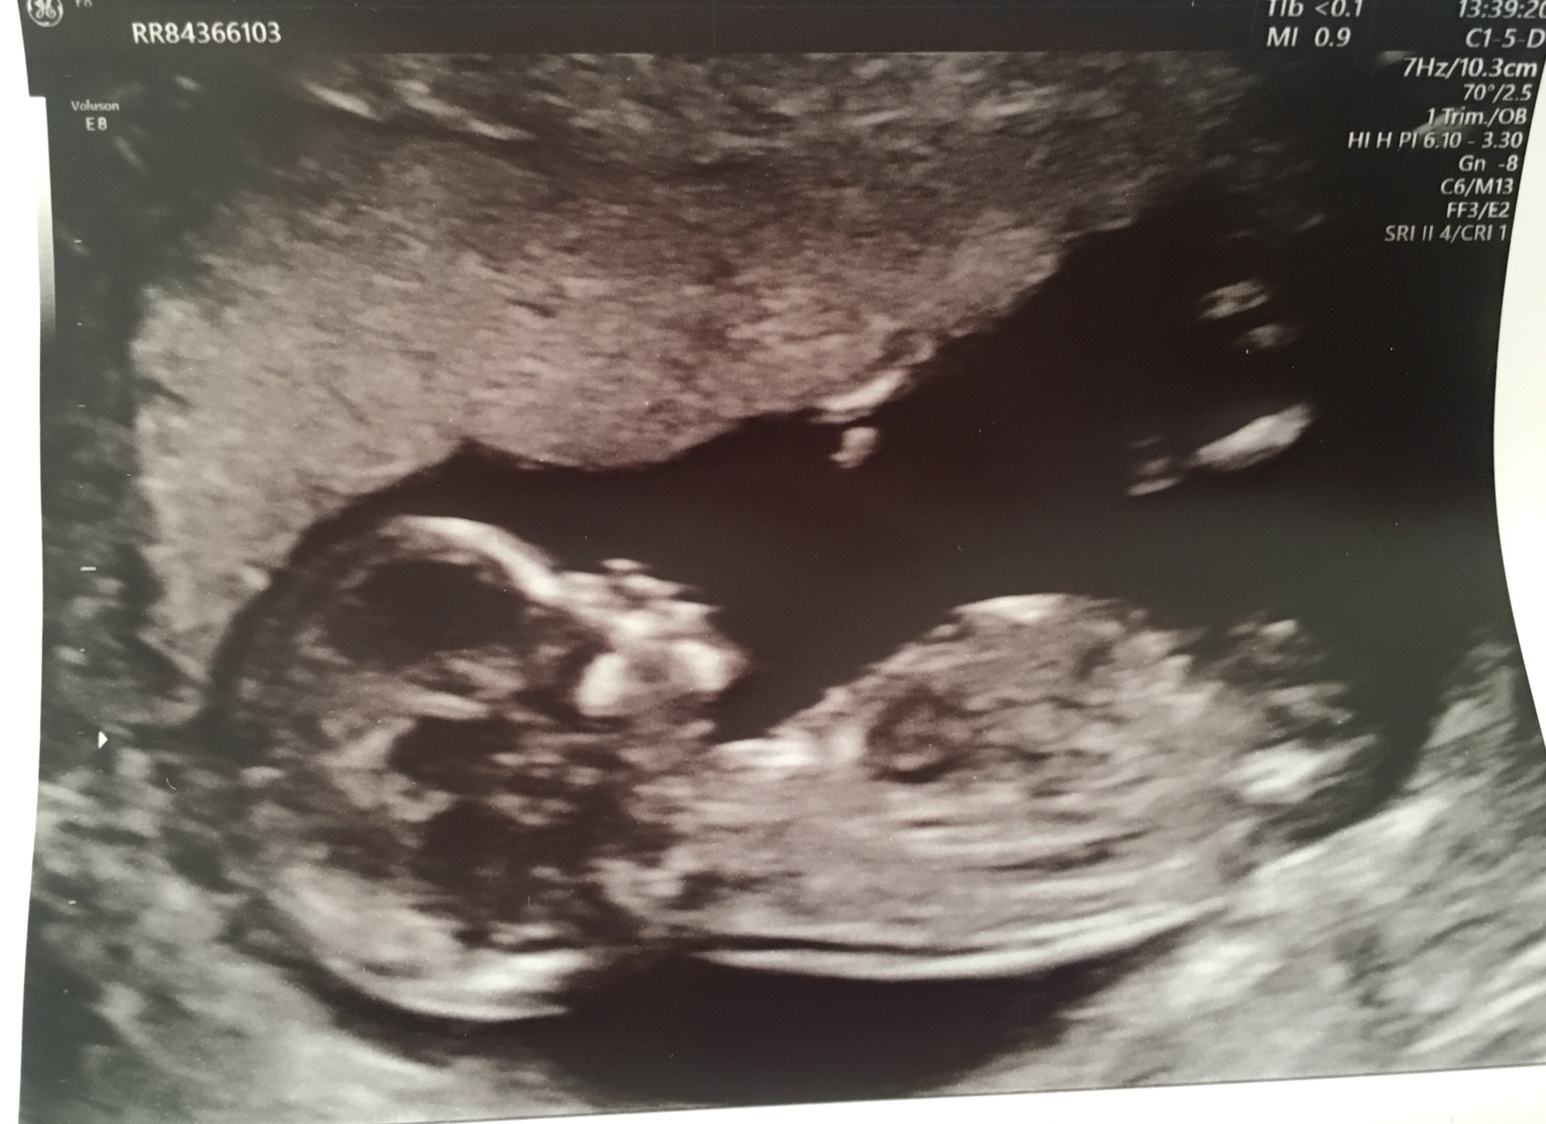

Here is my confusion...... I don’t even know where the nub is [emoji85]Attachment 40454

The nub is where the bottom arrow is pointing. Looks girly!

Thank you for taking the time to look. I swayed girl so I would be over the moon. Is the first arrow a leg?!

Tentative pink lean. It's not that absolutely classic shot I like to see but it does look girly.

I think the top arrow is cord.